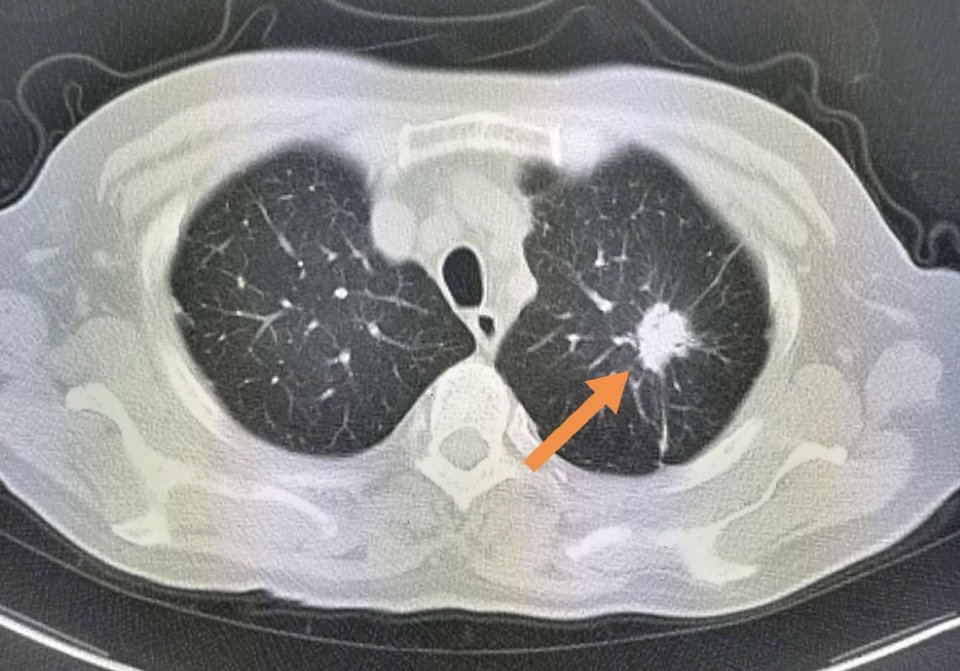

这位病人是一位78岁的老爷子,体检发现左肺不规则结节,有毛刺,有胸膜牵拉,高度怀疑肺癌。

但是增强扫描发现病灶没有任何强化,说明病灶没有供血血管,提示这是一个结核球(结核杆菌会破坏一切,形成局部干酪样坏死,没有血管所以增强扫描不强化;少数活动期病灶可以周边包膜样强化;极少数明显均匀强化)。

后来进一步穿刺证实为结核性肉芽肿,避免了挨一刀。